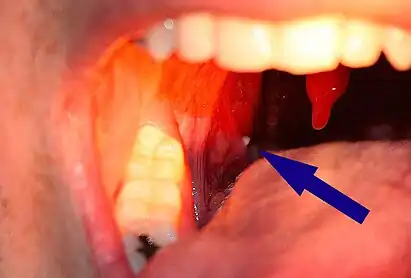

A tonsillolith lodged in the tonsillar crypt

Tonsil stones, also known as tonsilloliths, are mineralizations of debris within the crevices of the tonsils.[1][3] When not mineralized, the presence of debris is known as chronic caseous tonsillitis (CCT).[1] Symptoms may include bad breath,[1] foreign body sensation, sore throat, pain or discomfort with swallowing, and cough.[4] Generally there is no pain, though there may be the feeling of something present.[1] The presence of tonsil stones may be otherwise undetectable, however some people have reported seeing white material in the rear of their throat.

Tonsilloliths or tonsil stones are calcifications that form in the crypts of the palatal tonsils. They are also known to form in the throat and on the roof of the mouth. Tonsils are filled with crevices where bacteria and other materials, including dead cells and mucus, can become trapped. When this occurs, the debris can become concentrated in white formations that occur in the pockets.[12] Researchers found aerobic bacteria present on the surface of tonsilloliths and anaerobic bacteria at the core of tonsilloliths. They have the potential to cause oral halitosis as they contain volatile sulfur compounds and sulfur derived gases, foul smelling compounds produced during bacterial metabolism.[16] Tonsilloliths are formed when this trapped debris accumulates and are expressed from the tonsil. They are generally soft, sometimes rubbery. This tends to occur most often in people who suffer from chronic inflammation in their tonsils or repeated bouts of tonsillitis.[12] They are often associated with post-nasal drip.